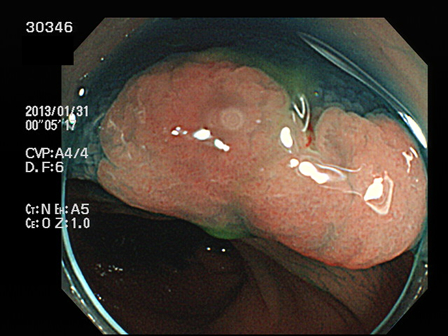

上記100名より抽出した平坦・陥凹型腺腫(=癌化の危険が高いが見落としやすい病変)の内視鏡写真

30346 30347 30348 30349 30350 30353 30356 30357 30360 30361 30363 30365